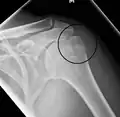

Types of major humerus fractures

Proximal

Proximal humerus fractures most often occur among elderly people with osteoporosis who fall on an outstretched arm.[9] Less frequently, proximal fractures occur from motor vehicle accidents, gunshots, and violent muscle contractions from an electric shock or seizure.[10][5] Other risk factors for proximal fractures include having a low bone mineral density, having impaired vision and balance, and tobacco smoking.[11] A stress fracture of the proximal and shaft regions can occur after an excessive amount of throwing, such as pitching in baseball.[6]

Definitive diagnosis of humerus fractures is typically made through radiographic imaging. For proximal fractures, X-rays can be taken from a scapular anteroposterior (AP) view, which takes an image of the front of the shoulder region from an angle, a scapular Y view, which takes an image of the back of the shoulder region from an angle, and an axillar lateral view, which has the patient lie on his or her back, lift the bottom half of the arm up to the side, and have an image taken of the axilla region underneath the shoulder.[9] Fractures of the humerus shaft are usually correctly identified with radiographic images taken from the AP and lateral viewpoints.[12] Damage to the radial nerve from a shaft fracture can be identified by an inability to bend the hand backwards or by decreased sensation in the back of the hand.[5] Images of the distal region are often of poor quality due to the patient being unable to extend the elbow because of pain. If a severe distal fracture is suspected, then a computed tomography (CT) scan can provide greater detail of the fracture. Nondisplaced distal fractures may not be directly visible; they may only be visible due to fat being displaced because of internal bleeding in the elbow.[7]

Humerus fractures are among the most common of fractures. Proximal fractures make up 5% of all fractures and 25% of humerus fractures,[9] middle fractures about 60% of humerus fractures (12% of all fractures),[12] and distal fractures the remainder. Among proximal fractures, 80% are one-part, 10% are two-part, and the remaining 10% are three- and four-part.[22] The most common location of proximal fractures is at the surgical neck of the humerus.[3] Incidence of proximal fractures increases with age, with about 75% of cases occurring among people over the age of 60.[11] In this age group, about three times as many women as men experience a proximal fracture.[23] Middle fractures are also common among the elderly, but they frequently occur among physically active young adult men who experience physical trauma to the humerus.[12] Distal fractures are rare among adults, occurring primarily in children who experience physical trauma to the elbow region.[7]